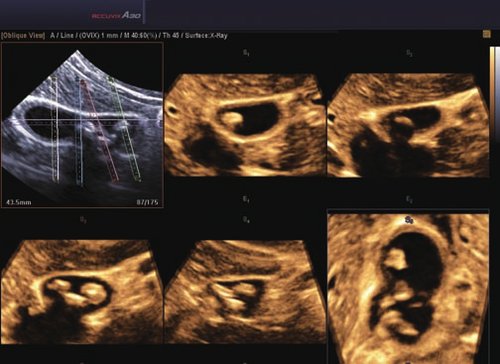

Das Samsung Accuvix A30 ist ein hochwertiges Ultraschallsystem, das mit seiner 3D-Technologie herausragende Ergebnisse ermöglicht. Das Sonographiegerät besitzt 5 Sondenanschlüsse und ist mit 20 unterschiedlichen Schallköpfen kompatibel. Mit dem A30 können Schallköpfe vom Typ Konvex, Mikrokonvex, 3D-Konvex, CW, Phased Array, Linear und Endokavitär verwendet werden. Bei zwei der Sonden handelt es sich um S-VUE Ultraschallsonden, die durch ihre höhere Bandbreite noch feinere Scans erzeugen.

Das Ultraschallsystem hebt sich besonders durch seine 3D-Technologie wie die Face Auto Detection für detaillierte Ultraschallbilder von Föten oder das Volume Shade Imaging, das sich auf die lebensnahe Darstellung von Schattierungen und Hauttönen fokussiert, ab. Mit weiteren wertvollen Technologien wie dem ElastoScan™ werden Tumore schneller erfasst und durch die HD Volumen Bildgebung sowie das DMR+™ eine erstklassige Bildqualität erzielt.

• 3D-Bildmodus

• 4D-Bildmodus.

• FAD™, die Face Auto Detection, stellt das Gesicht eines Fötus besonders detailliert dar. Überflüssige Daten werden entfernt und ein besonders realistisches Bild gezeichnet.

• Volume Shade Imaging, kurz VSI™, visualisiert ein 3D-Bild, das Hauttöne und Schattierungen auf ein qualitativ neues Niveau hebt.